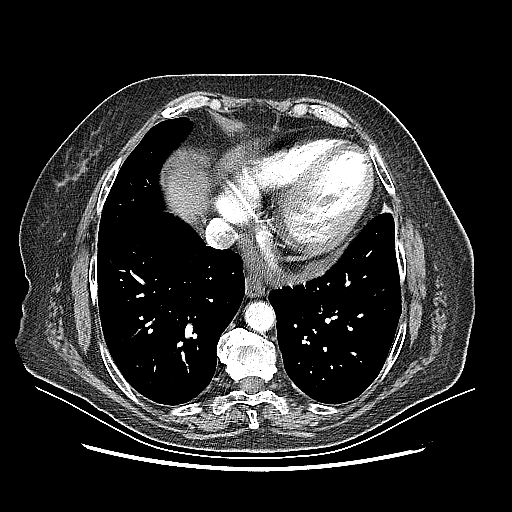

Reconstructed NATIVE CT scan (cycle consistency)

Full window (WL 1023.5, WW 4095 β†’ Low βˆ’1024, High +3071)

Lung window (WL -600, WW 1500 β†’ Low βˆ’1350, High +150)

Mediastinum window (WL 40, WW 400 β†’ Low βˆ’160, High +240)